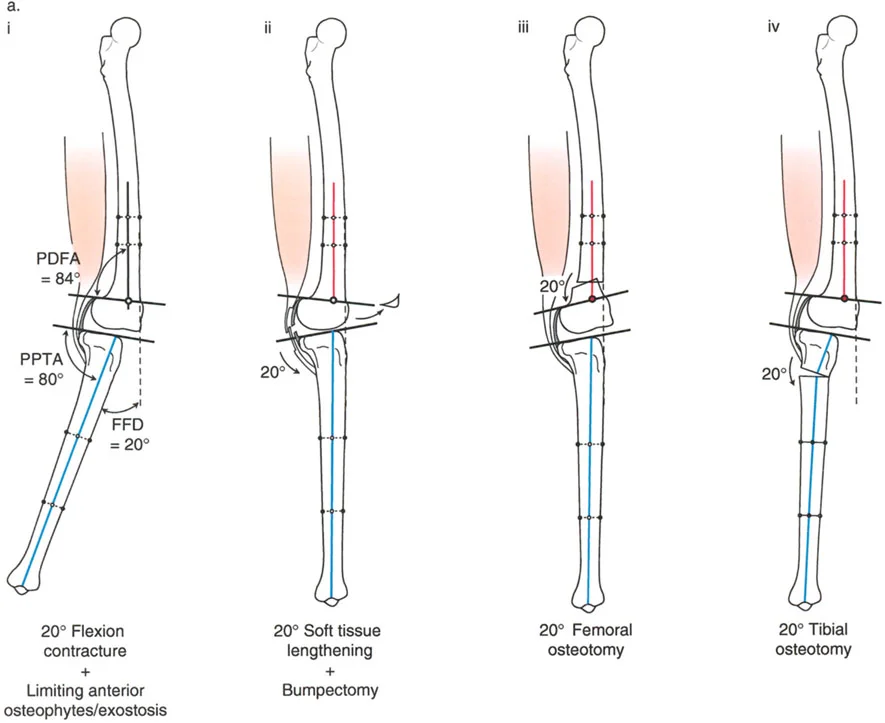

تصحيح تحدد حركة الركبة (Flexion Deformity - FFD)

تحدُّد حركة الركبة هو عدم القدرة على مد الركبة بالكامل. يمكن أن يكون سببه عظميًا أو ناتجًا عن تقلص في الأنسجة الرخوة.

- التشخيص الدقيق: يجب تحديد ما إذا كان تحدد الحركة ناتجًا عن تشوه عظمي (تقوس أمامي في الفخذ أو الساق) أو تقلص في الأنسجة الرخوة (الأوتار الخلفية، محفظة المفصل).

- قطع العظم التمديدي (Extension Osteotomy):

- إذا كان التشوه عظميًا، يتم إجراء قطع عظم تمديدي في عظم الفخذ أو الساق لتصحيح التقوس.

- الأستاذ الدكتور محمد هطيف يؤكد على أهمية عدم تصحيح الساق بأكثر من 90 درجة PPTA لتجنب فقدان الميل الخلفي الطبيعي للساق.

- تحرير الأنسجة الرخوة (Soft Tissue Release):

- إذا كان السبب هو تقلص الأنسجة الرخوة، فقد يتم إجراء إطالة للأوتار أو تحرير لمحفظة المفصل.

- إزالة النتوءات العظمية (Osteophyte Resection):

- إذا كانت النتوءات العظمية الأمامية تمنع المد الكامل، يمكن إزالتها جراحيًا.

- التصحيح التدريجي: في حالات تحدد الحركة الشديدة أو المعقدة، قد يكون التصحيح التدريجي باستخدام التثبيت الخارجي هو الخيار الأكثر أمانًا.